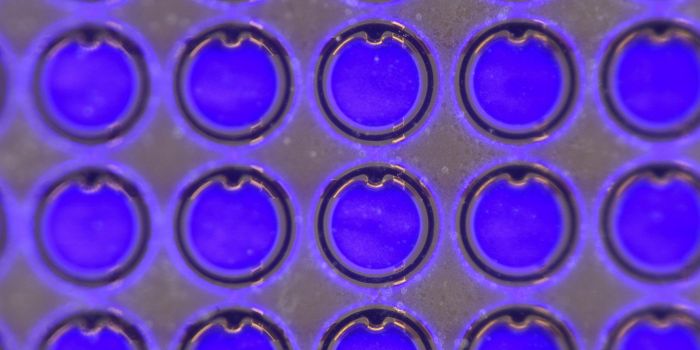

MAY 05, 2024Health & MedicineHamburg, April 2024 Our customers depend on the high performance and reliability of the plates used in their high-throug ...